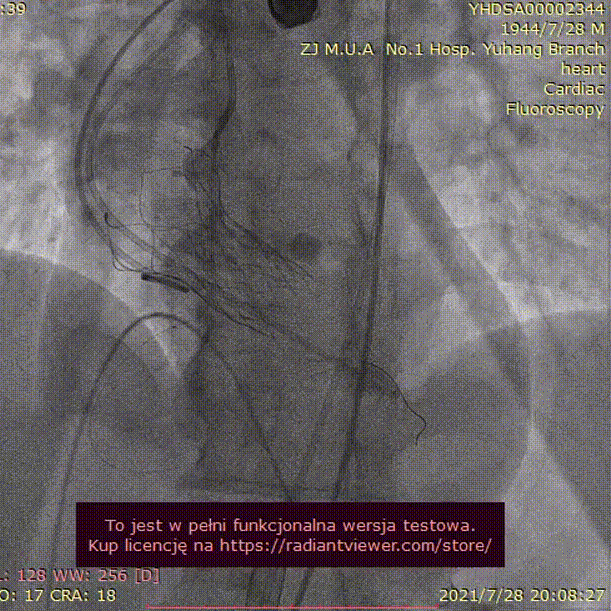

手术过程:

20mm球囊预扩

(无腰征,少量瓣周漏)

TAV24 瓣膜释放前定位

释放过程

植入后造影

术后压差1mmHg

术后结果:测左室-主动脉平均跨瓣压差3mmHg。

术中经食道心超评估: